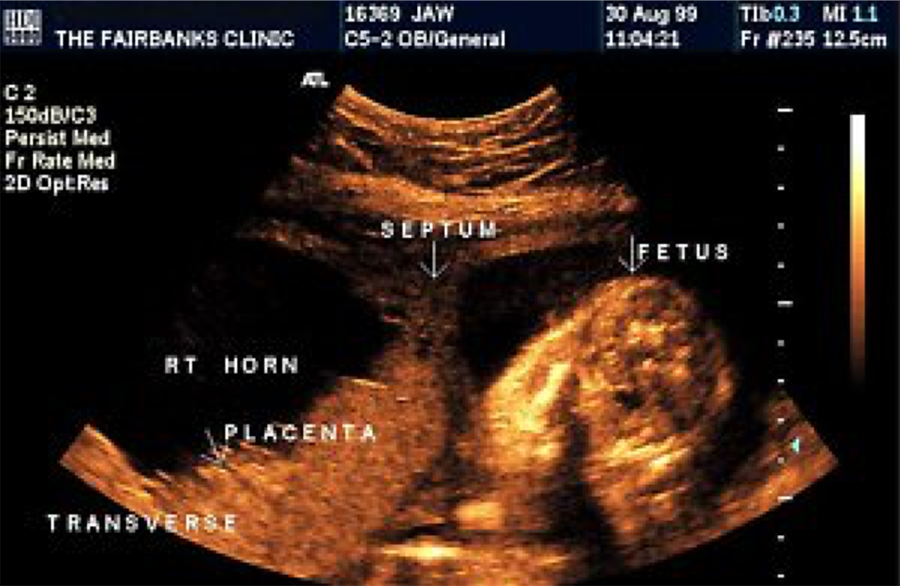

Synechial band/ amniotic shelf Medical ultrasound, Ultrasound

Recognizing Intraamniotic Bandlike Structures on Obstetric Ultrasound